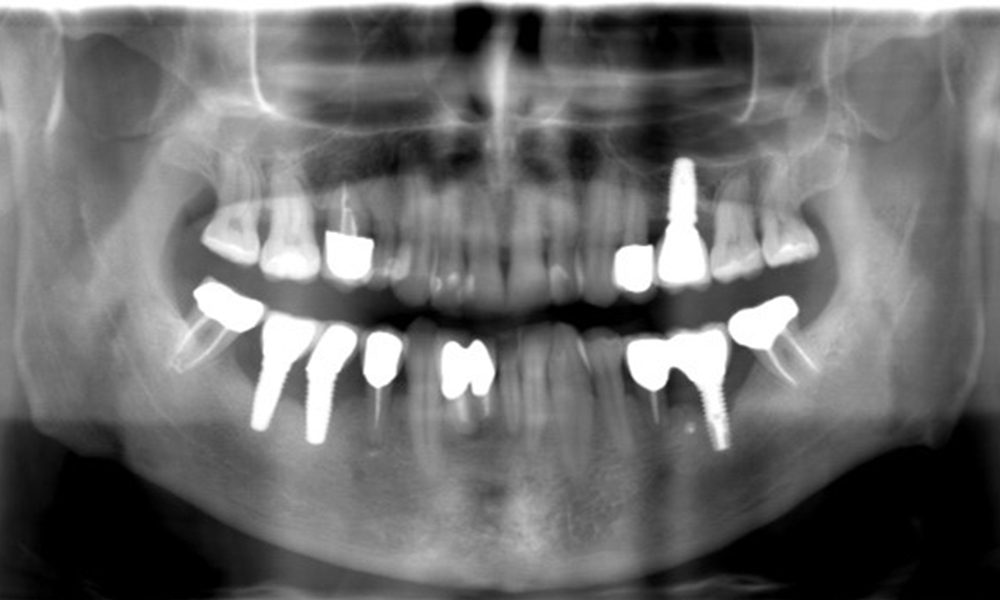

The X-ray images show the progression of bone loss. OPG from 29.06.2020 (left) and OPG from 26.02.2024 (right).

The X-ray images show the progression of bone loss.

The X-ray images show the progression of bone loss in the area of the implant in region 36: dental film from 11.02.2021 (left) and dental film from 18.01.2024 (right).